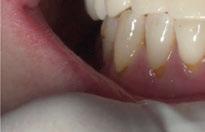

A partir del estudio radiológico y de las imágenes fotográficas podemos observar edentulismo de 17, 15, 14, 12,

25, 26, 28, 37, 38, 47 y 48. Presentaba corona desajustada en 13 con extensión en 12, implantes en 35-36, 45-46, con coronas ferulizadas en 35-36, 45-46, y dientes anteriores superiores con enfermedad periodontal Grado IV.

2. Exploración de tejidos blandos

El paciente presentaba biotipo periodontal grueso, con márgenes asimétricos, con recesiones gingivales a nivel de 11 y 13 y pérdida de tejidos blandos interproximales.